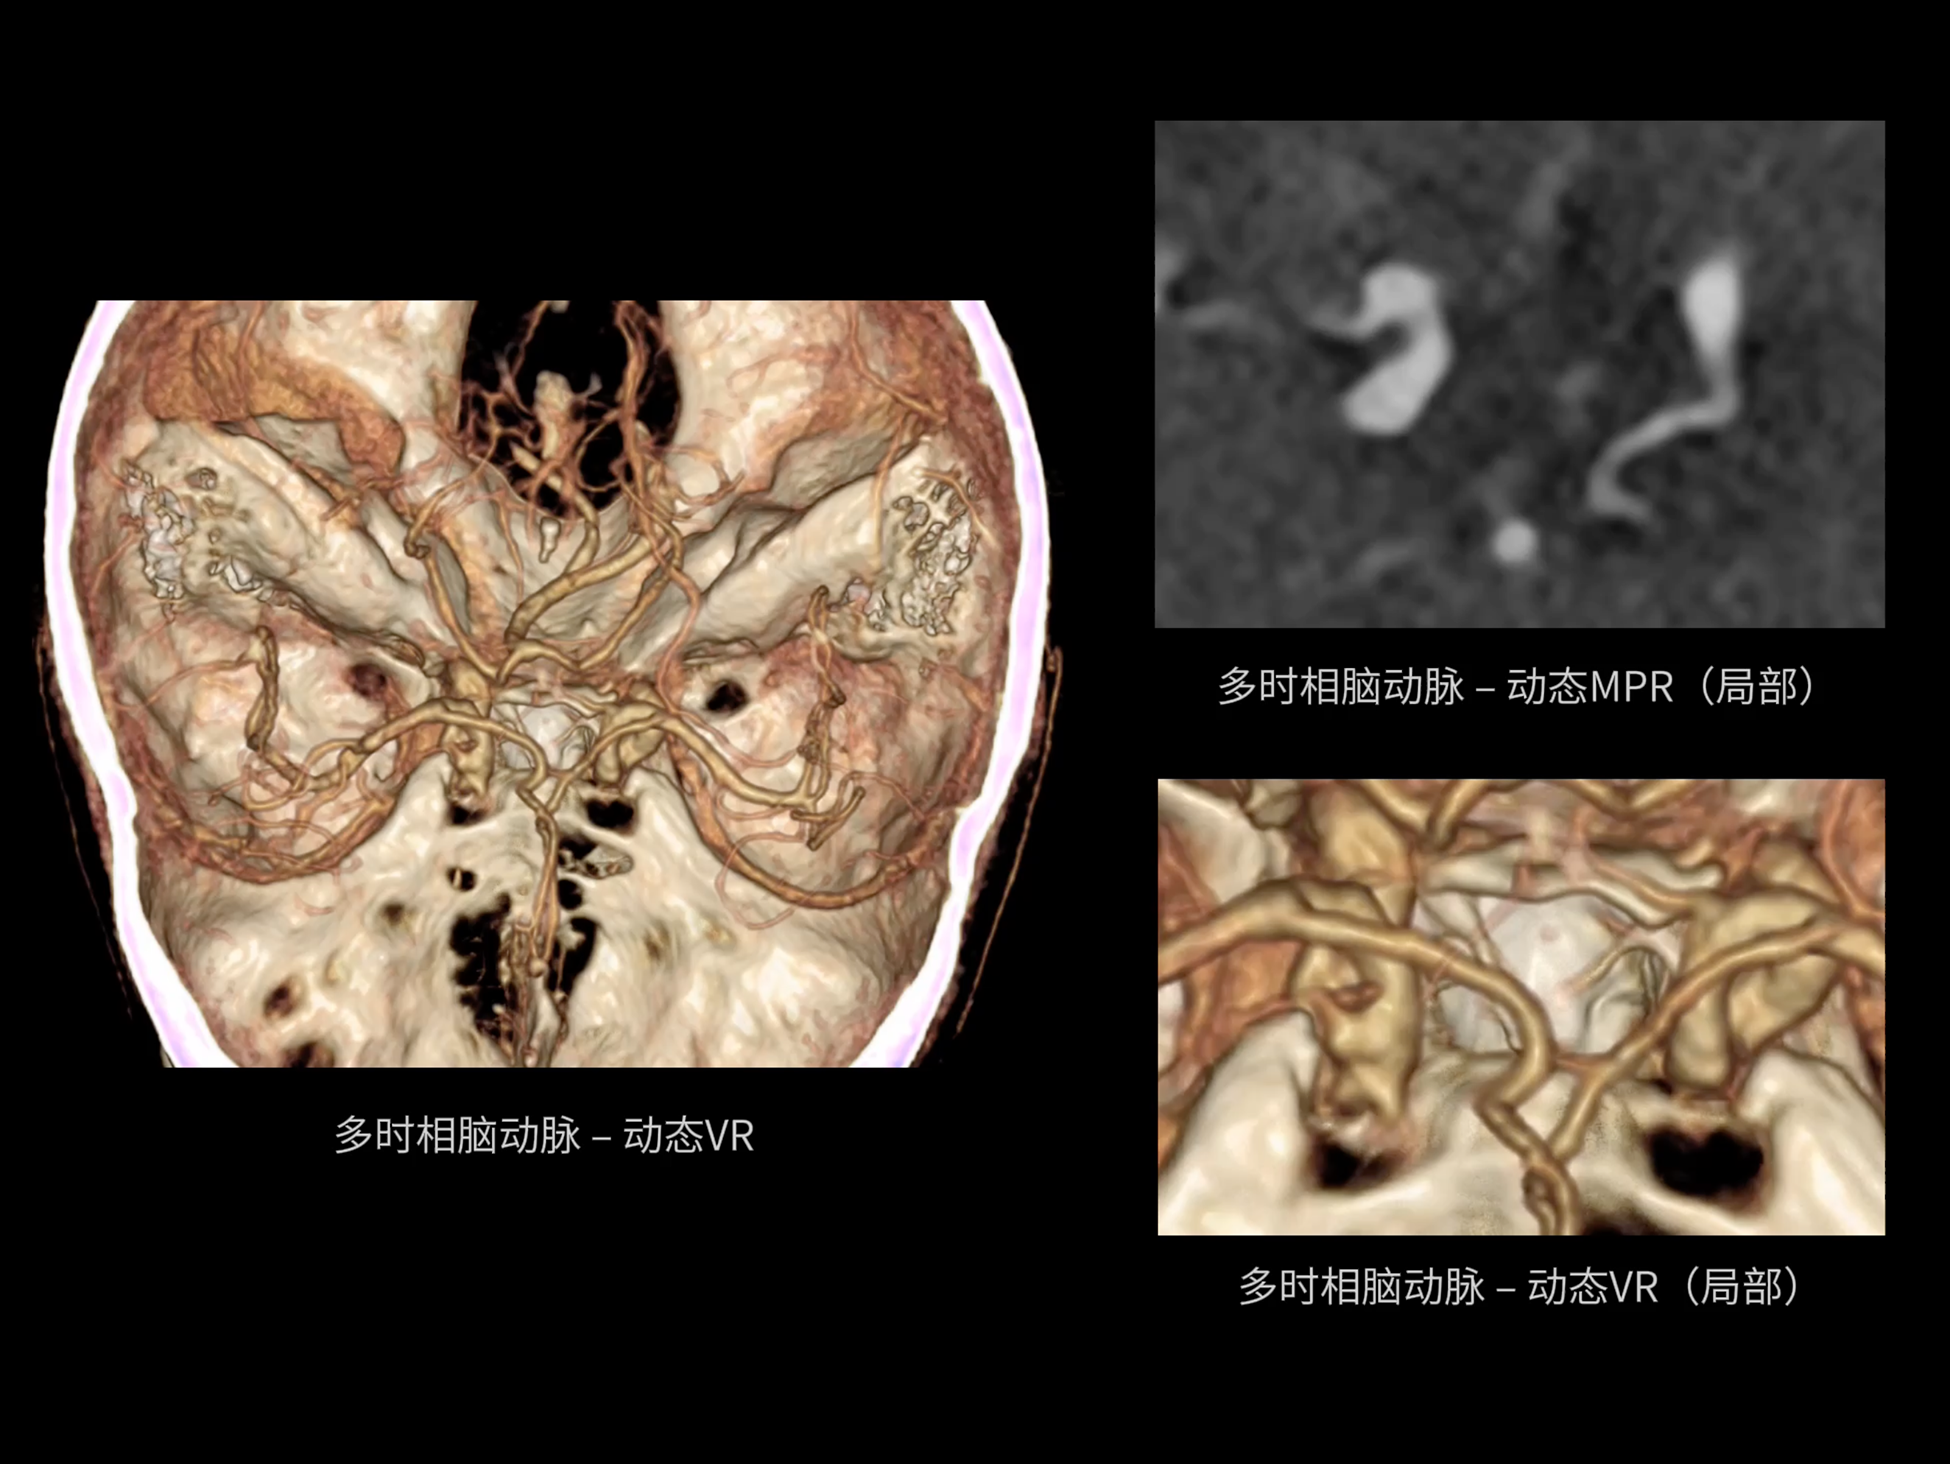

全域能谱

uCT SiriuX® 依托16cm超宽探测器与双源能谱技术,实现真正意义上的全身高清能谱成像。单次扫描同步获取灌注、能谱等多维定量参数,精准解析组织特性与病灶成分,为临床决策提供更深层次的诊断依据。

全身高清能谱成像

uCT SiriuX® 采用独有的双宽体探测器设计,实现470mm超大视野与全脏器容积覆盖的能谱成像,轻松应对不同体型患者和扫描部位应用需求。配合创新能谱重建影像链与精准双能数据配准,系统可有效抑制伪影、提升信噪比,在全脏器范围内提供高质量能谱图像,显著拓展临床精准诊断的广度与深度。

能谱成像可揭示丰富的物质与能量信息,其临床价值的充分释放有赖于完善高效的后处理分析平台。uCT SiriuX® 提供全面能谱高级分析工具,覆盖心血管、肿瘤、神经、骨科等多类临床场景。平台支持动脉增强分数分析(AEF)、细胞外容积分析(ECV)、肿瘤同源性分析、肺栓塞分析、骨髓水肿分析等多项评估,并提供多达10种基物质对成像,为精准诊断与科研探索提供坚实支撑。